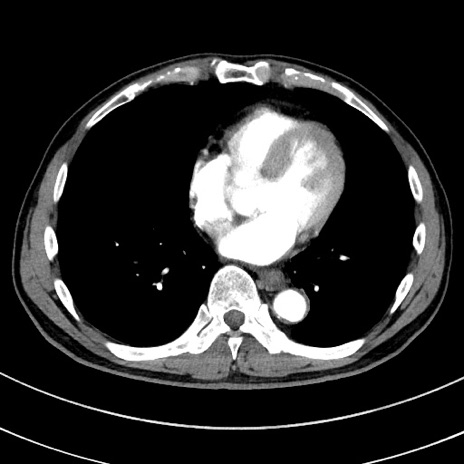

症例8(横断像)

【症例】 60歳代男性

【主訴】 黒色吐物

【現病歴】 4日前から嘔気自覚、2日前の朝食後にも嘔気あり、自分で手で嘔吐反射起こし嘔吐したところ血が混ざっていたため受診。

【既往歴】 5年前汎発性腹膜炎を伴う急性虫垂炎で手術、高血圧、前立腺肥大症、高脂血症

【身体所見】 腹部正中に手術癩痕あり 腹部平坦・軟圧痛なし膨満感あり

【データ】WBC 8400、CRP 4.54